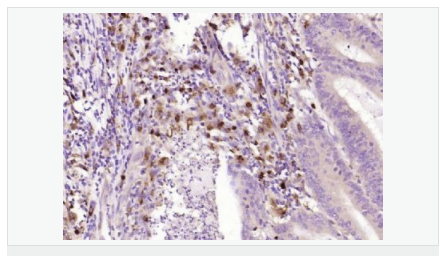

| 英文名稱(chēng) | SPR |

| 中文名稱(chēng) | 墨蝶蛉還原酶抗體 |

| 別 名 | SDR38C1; Sepiapterin reductase (7,8 dihydrobiopterin:NADP+ oxidoreductase); Sepiapterin reductase; Short chain dehydrogenase/reductase family 38C, member 1; SPR; SPRE_HUMAN. |

| 研究領(lǐng)域 | 腫瘤 細胞生物 神經(jīng)生物學(xué) 信號轉導 新陳代謝 |

| 產(chǎn)品應用 | WB=1:500-2000 ELISA=1:5000-10000 IHC-P=1:100-500 IHC-F=1:100-500 ICC=1:100-500 IF=1:100-500 (石蠟切片需做抗原修復) not yet tested in other applications. optimal dilutions/concentrations should be determined by the end user. |

| 分 子 量 | 28kDa |

| 細胞定位 | 細胞漿 |

| 免 疫 原 | KLH conjugated synthetic peptide derived from human Sepiapterin reductase:101-200/261 |

| 產(chǎn)品介紹 | This gene encodes an aldo-keto reductase that catalyzes the NADPH-dependent reduction of pteridine derivatives and is important in the biosynthesis of tetrahydrobiopterin (BH4). Mutations in this gene result in DOPA-responsive dystonia due to sepiaterin reductase deficiency. A pseudogene has been identified on chromosome 1. [provided by RefSeq, Jul 2008] Function: Catalyzes the final one or two reductions in tetra-hydrobiopterin biosynthesis to form 5,6,7,8-tetrahydrobiopterin. Subunit: Homodimer. Subcellular Location: Cytoplasm. Post-translational modifications: In vitro phosphorylation of Ser-213 by CaMK2 does not change kinetic parameters. DISEASE: Defects in SPR are the cause of dystonia DOPA-responsive due to sepiapterin reductase deficiency (DRDSPRD) [MIM:612716]. In the majority of cases, patients manifest progressive psychomotor retardation, dystonia and spasticity. Cognitive anomalies are also often present. The disease is due to severe dopamine and serotonin deficiencies in the central nervous system caused by a defect in BH4 synthesis. Dystonia is defined by the presence of sustained involuntary muscle contractions, often leading to abnormal postures. Similarity: Belongs to the sepiapterin reductase family. SWISS: P35270 Gene ID: 6697 Database links: Entrez Gene: 6697 Human Omim: 182125 Human SwissProt: P35270 Human Unigene: 301540 Human Important Note: This product as supplied is intended for research use only, not for use in human, therapeutic or diagnostic applications. |